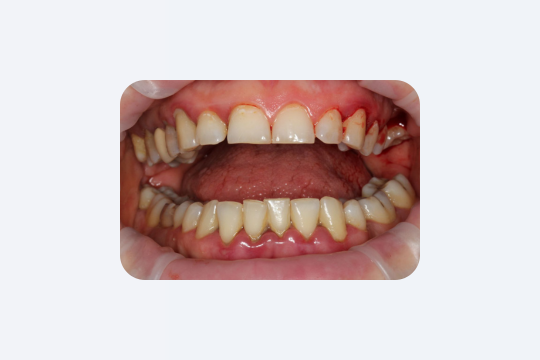

2. Пародонтит без боли

Воспаление дёсен (гингивит, пародонтит) в начале часто почти бессимптомное. В то же время любое кровоточивость при чистке зубов — это явный признак воспаления.

Исследования показывают, что люди, которые замечают кровь на зубной щётке, значительно чаще имеют гингивит или пародонтит. Простое игнорирование присутствия крови = игнорирование проблемы.

В запущенных случаях «скрытая рана» пародонта может иметь большую площадь. Обследования показывают, что у больных тяжёлым пародонтитом суммарная площадь эрозированной поверхности дёсен может достигать десятков см², сравнимо с площадью ладони. Через эту «поверхность язв» бактерии и их токсины попадают прямо в кровоток. То есть хронический пародонтит сам по себе является источником системного воспаления. Его осложнения — от повышенного риска инфарктов до ухудшения контроля сахара — хорошо известны стоматологам и терапевтам.